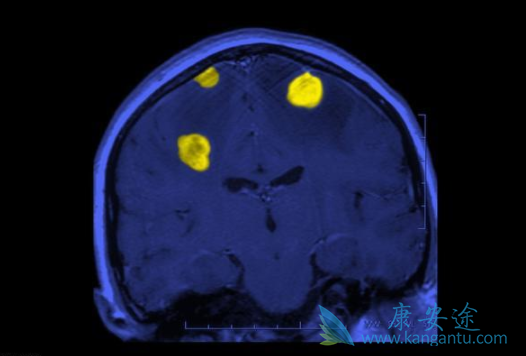

有些靶向药物的长期应用可导致神经系统的不良反应,虽然并不常见,但若发生时处理不当,可使患者留下神经系统后遗症甚至导致死亡,故应当引起足够的重视。可逆性后脑白质病综合征(RPLS)是VEGF抑制剂的一种少见但是十分严重的不良反应,最早见于贝伐单抗,发生率约为0.1%,其主要表现为头痛、癫痫发作、嗜睡、不同程度意识障碍及视觉异常。

治疗应去除病因,再对症处理,一旦经影像学确诊发生RPLS,应立即停药,再给予降压等对症治疗,一般会在数天内好转,此病预后良好。进行性多灶性白质脑病(PML)是一种亚急性脱髓鞘性疾病,常见于免疫系统功能受到严重抑制的患者,最常出现的症状为视觉障碍、肌无力和认知功能的改变,其致死率高,大部分患者在发病后3-6个月内死亡。

进行性多灶性白质脑病的发病率虽然较低,但由于其病情进展迅速,且目前尚无可靠的预防措施及有效的治疗方法,患者的预后往往极差。在利妥昔单抗的治疗过程中,如果患者出现神经症状,应考虑请神经科医师会诊,并进行相关检查。对于确诊为PML的患者,应停止使用利妥昔单抗,同时采取积极的抗病毒治疗,以尽早重建机体免疫系统。